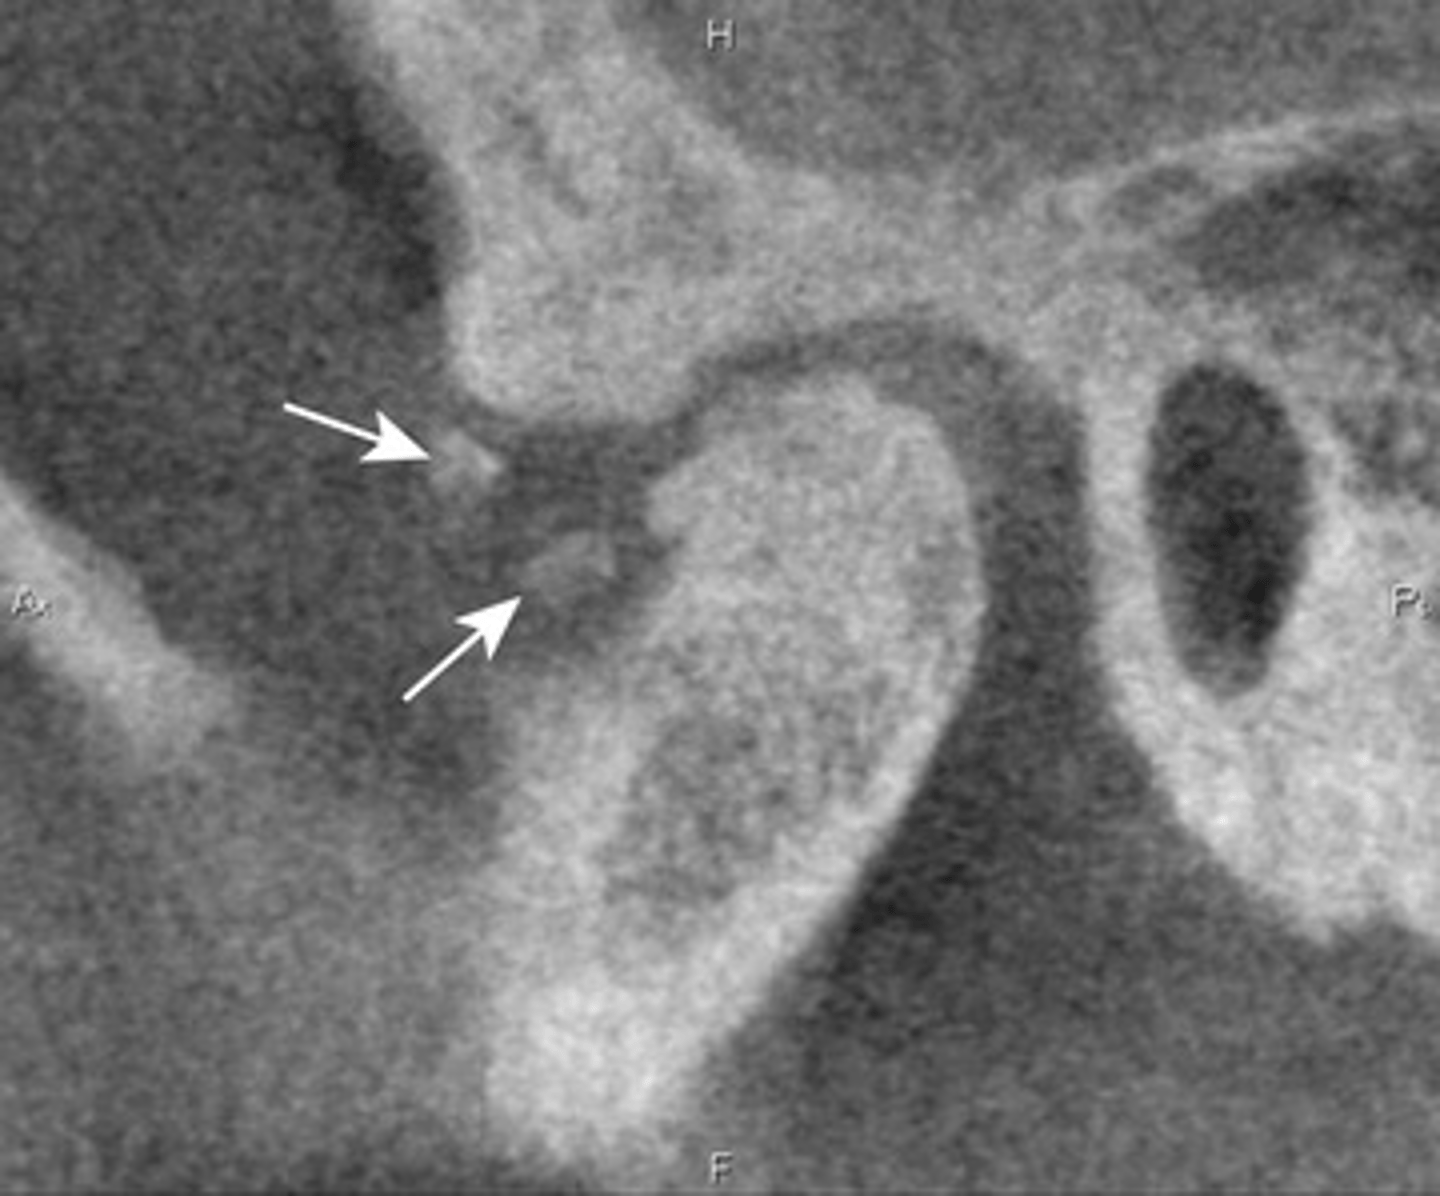

Patient has DJD.

The top images show the subchondral/ Ely cyst, a pseudocyst of connective tissue, granular tissue and osteoid, the bottom images show the same patients left side with broad erosion, a lack of cortication, loss of joint space.

Osteophytes- joint mice associated with DJD

What are the arrows showing?

Patient has DJD, there is significant erosion and loss of joint space.

A and B show prominent osteophyte formation at the anterior aspect

C shows multiple subchondral erosions

What is the diagnosis of the patient based off these radiographs and what are the features?